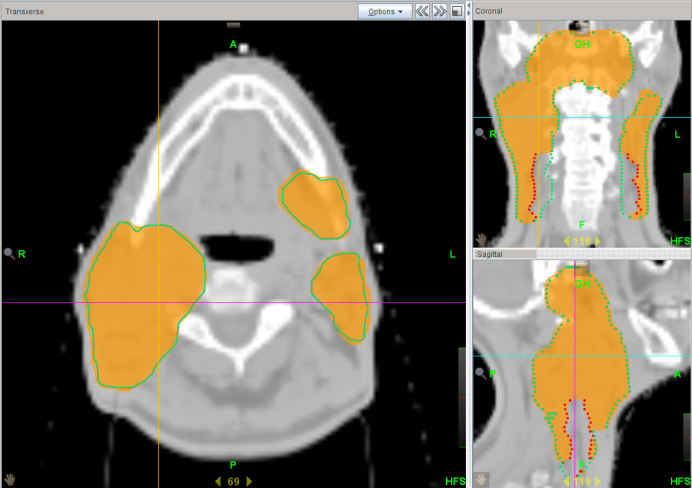

Beauty of Dose Painting

Chung Yin Mak

Score: 99.5/ 100

Hospital: St. Teresa’s Hospital

Technique: VMAT

Rank: 2017 Champion

Job Title: Radiation Therapist